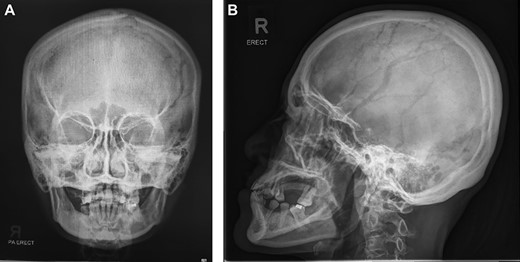

X-ray skull AP & lateral views (Fig. 1) did not show bony erosions, lytic lesions or sclerotic lesions which if present would indicate a possible infectious, inflammatory or neoplastic process. However, the bony swelling was difficult to assess on X-ray due to orientation.

A relatively normal X-ray skull which did not show any significant pathology.